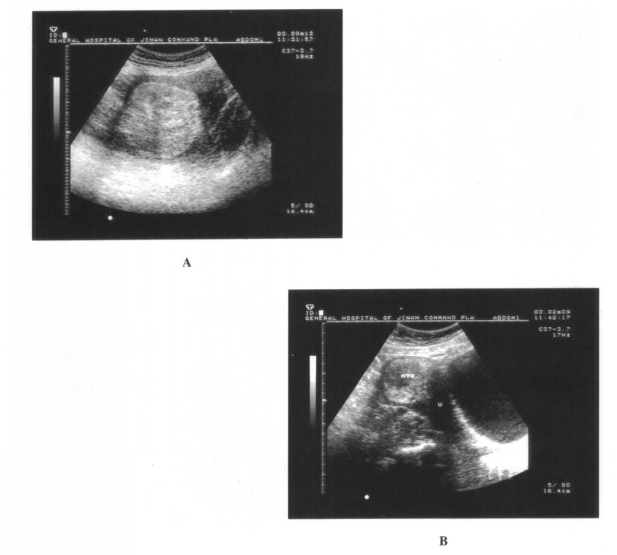

B超应用于临床以来,对子宫瘤的诊断与鉴别诊断起着重要的作用。而且有较高的诊断价值。...

B超检查可以显示子宫肌瘤引起的子宫增大、形状不规则,可以显示肌瘤的数目、生长的部位及大小,肌瘤是否液化变性,有没有压迫临近器官。...

B超是检查子宫肌瘤的首选辅助方法。腹部B超可以准确地判断肌瘤部位、大小和数目。...